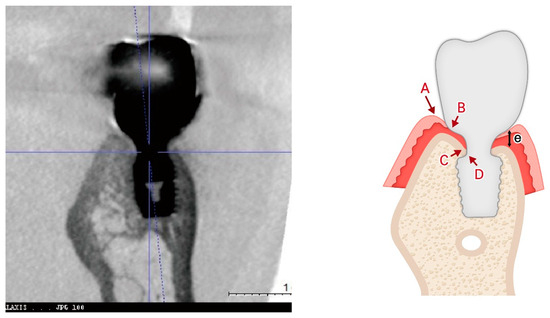

Figure 10 introduces a three-dimensional soft tissue analysis model (3DSTA) designed to quantify peri-implant soft tissue components using CBCT imaging. The left image represents a real CBCT scan, providing the foundation for the schematic. The right schematic model is derived from the CBCT image outlining the soft tissue structure around subcrestally placed implants (SPIs).

Figure 10.

Three-dimensional schematic model for 3D soft tissue analysis (3DSTA). This model, based on a real CBCT image (left), illustrates the key components of peri-implant soft tissue in a subcrestally placed implant (SPI). The schematic (right) highlights three zones: the sulcus zone (A–B), transitional zone (TZ, B–C), and subcrestal zone (SZ, C–D). The traditional biologic width (or STA) (e), observed in equicrestal implants, is shown for comparison. This model provides a framework for measuring peri-implant soft tissue dimensions using CBCT.